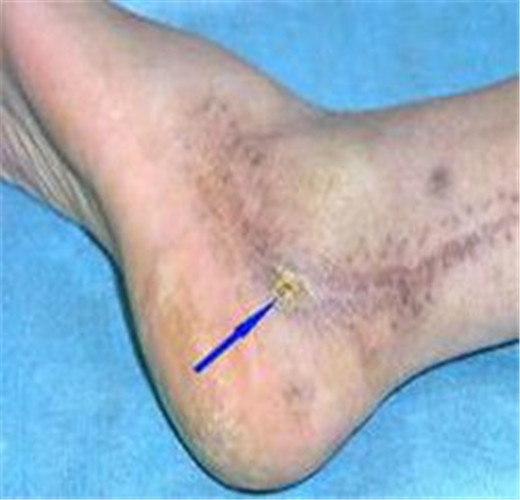

骨髓炎圖片

慢性骨髓炎腿部

慢性骨髓炎症狀表現